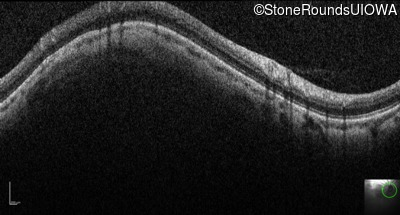

Optical Coherence Tomography - Left - 20/100

Exemplar